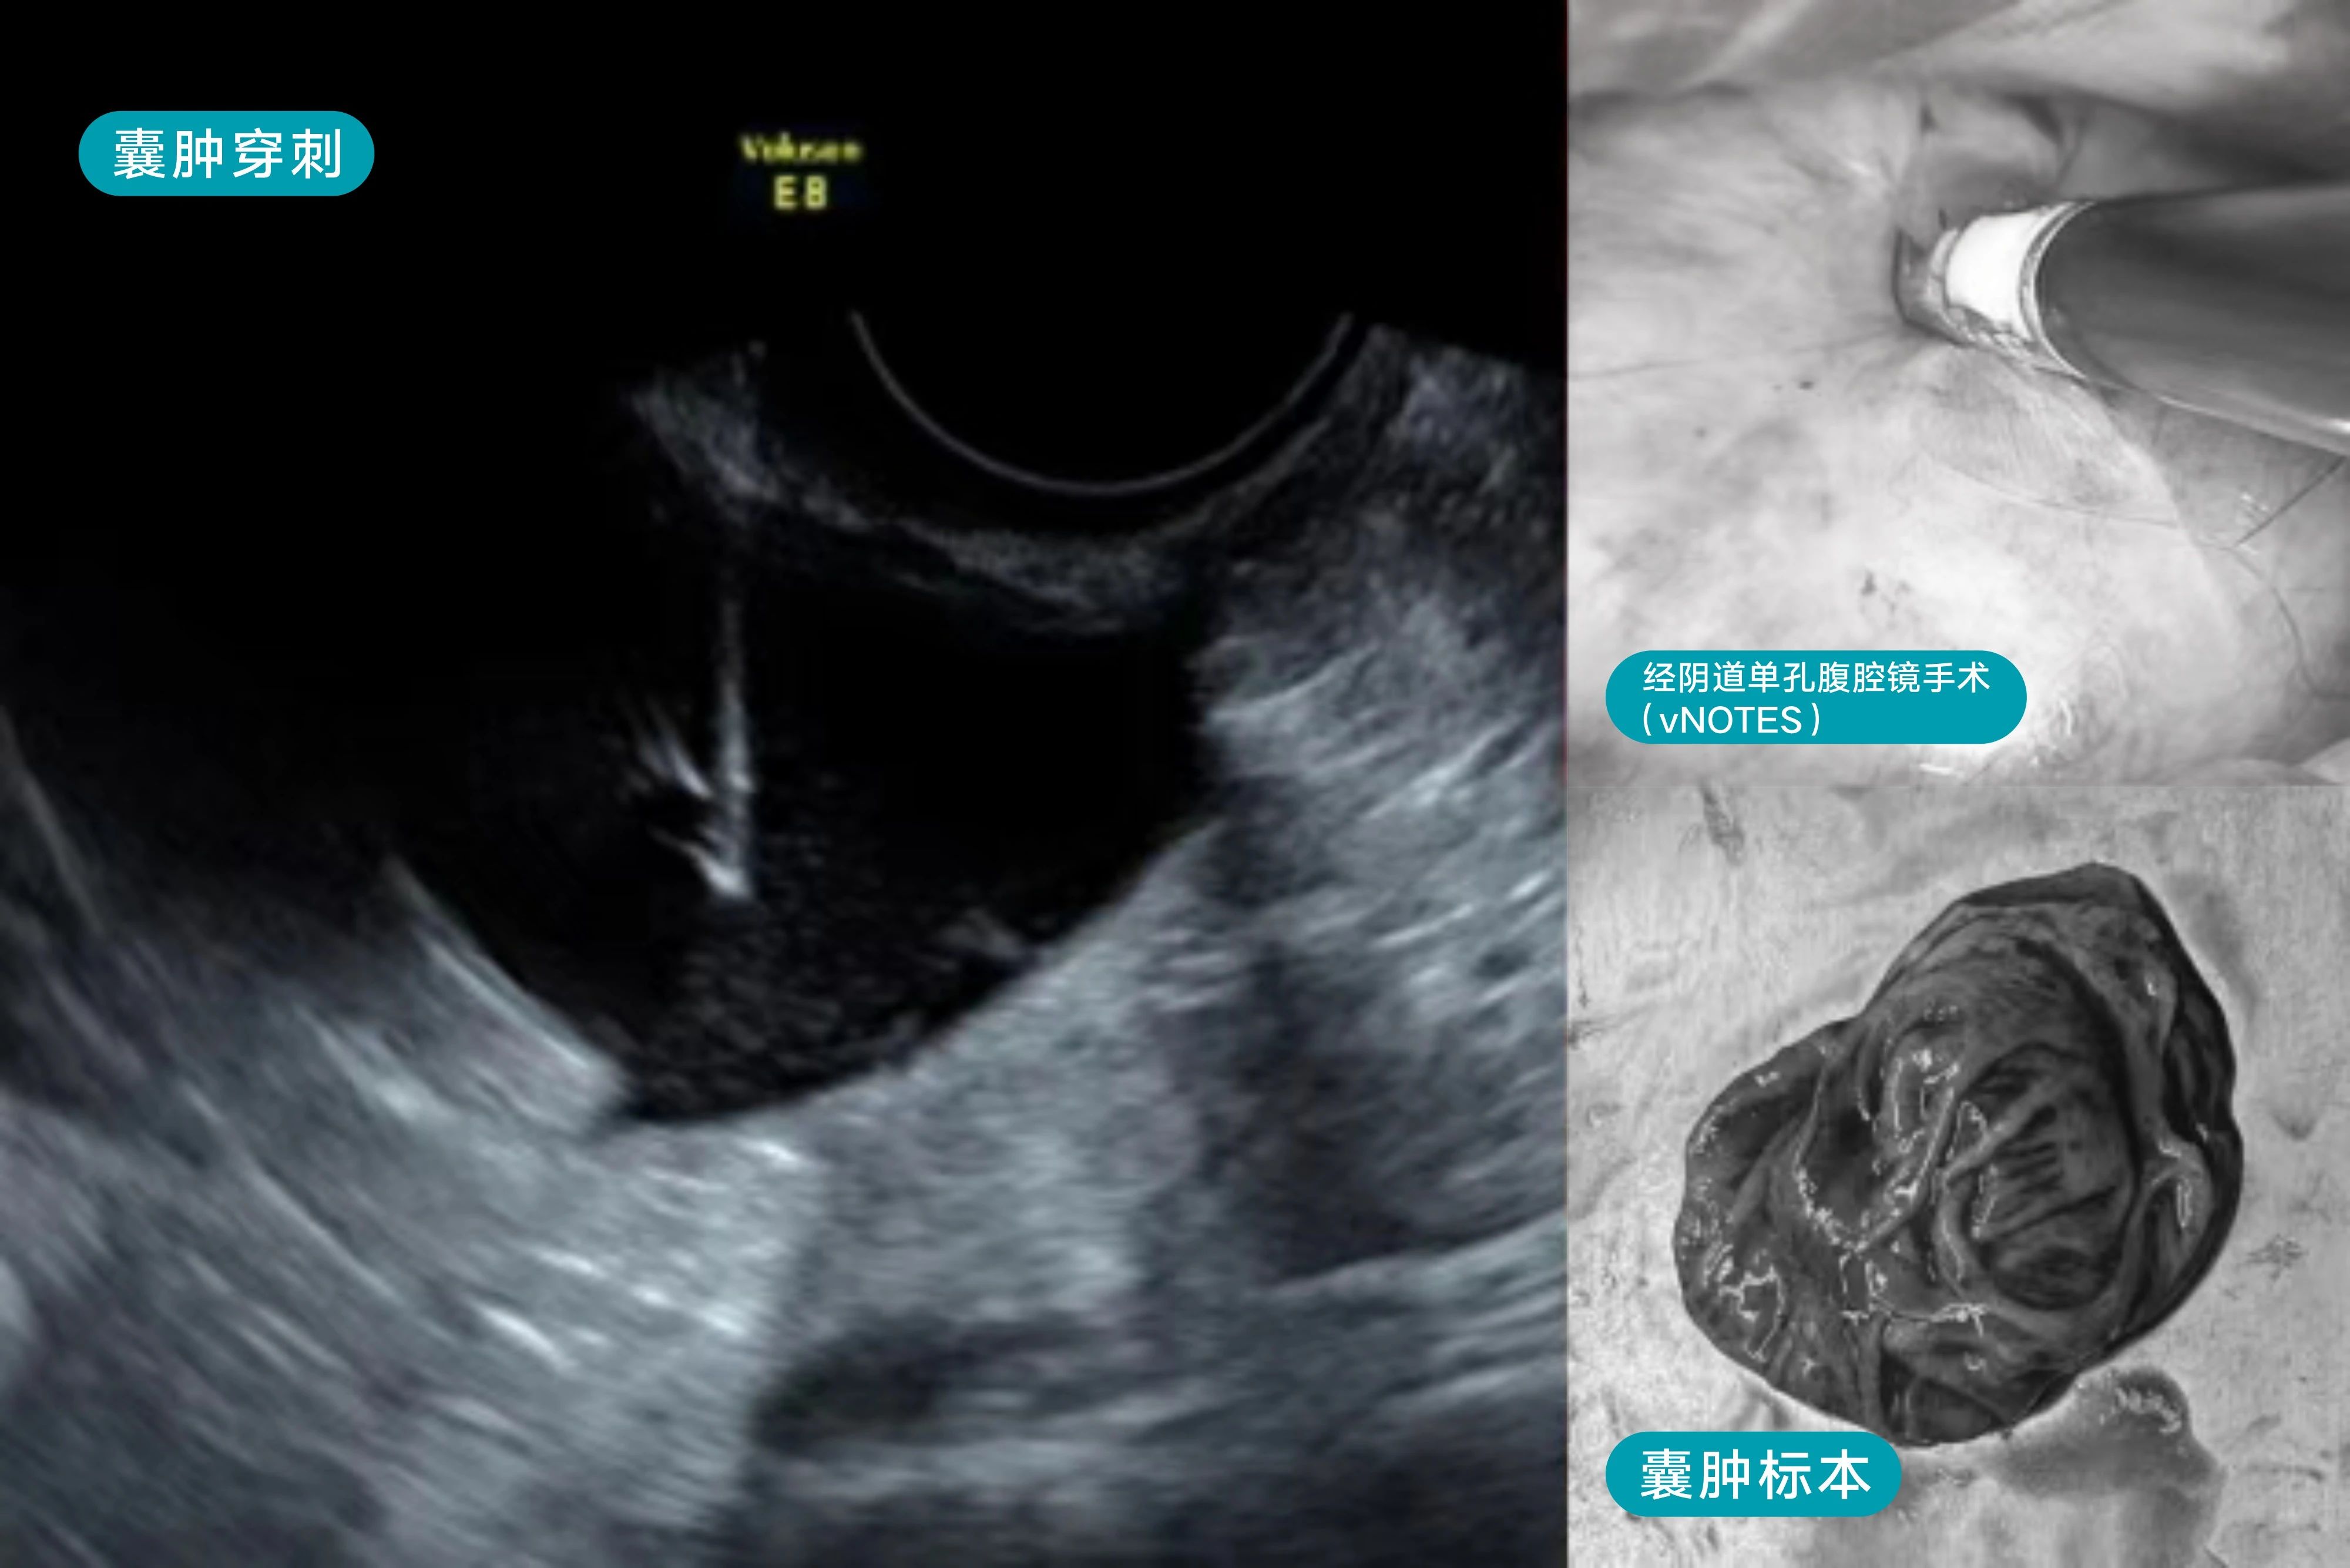

患者45岁,囊肿7cm,发现1年了,肿瘤标记物正常。

超声无法鉴别囊肿性质,无法确定是单纯囊肿、巧克力样囊肿还是卵巢肿瘤,术前龚晓明教授提前与客户沟通情况,并告知患者如果是粘液性囊肿(因粘液性囊腺瘤术后复发高),就需要行腹腔镜手术。考虑患者手术“无疤”需求,术中发现囊内液为粘液性后,立即中转经阴道单孔腔镜行患侧附件切除术及对侧输卵管切除术,满足了患者希望手术不留疤痕的要求,极大降低了患者罹患卵巢癌几率。

手术过程很顺利,患者术后当天下床自由活动。患者及家属既惊叹又感激,感谢龚晓明教授在治愈疾病的同时兼顾了患者爱美心理需求,真正做到了术后“无痕”!